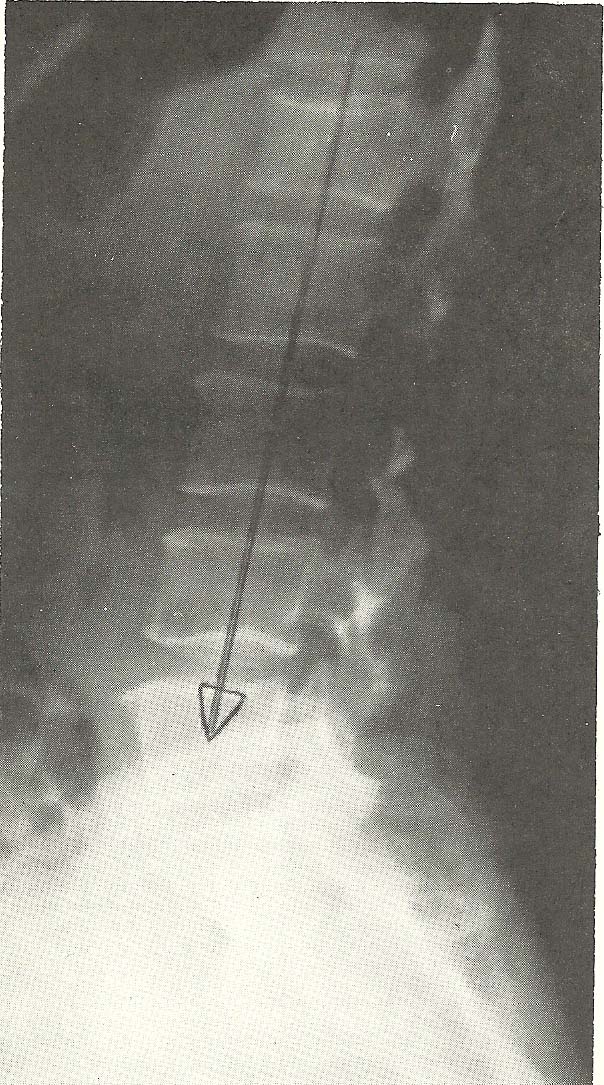

Case Illustrating Classifications A-5, A-6, A-8 and A-9

This case again shows coexistence of several classifications of

subluxations and serious alteration of mechanical functioning of the neck.

Cervical spine films revealed several abnormalities. Significant

generalized osteoporosis was evident by the relative radiolucency of osseous

structures and lack of trabeculations within the visualized bone. Spondylotic

hypertrophy and spurring of vertebral body margins were not severe but present

throughout the neck. Sclerosis of the articular facet surfaces is evidence of

degenerative joint disease. The disc narrowing at C4-C5, C5-C6, and C6-C7 is

noted. Several subluxations are apparent on the neutral lateral film alone

(Fig.  6.51). C2 shows slight anterior displacement upon C3, with C4 (A-5)

showing more anterior disrelationship relative to C5. C5 shows posterior

displacement upon C6 (A-6). The anterior carriage of the head alters the

cervical lordosis.

The lateral film taken during flexion of the neck fails to reveal

significant overall reduction in flexion, but a little flexion is seen at the

atlanto-occipital motion unit (Fig. 6.52). The anterior disrelationship of C2

upon C3 and C4 on C5 is not significantly altered during flexion, but the

posterior disrelationship of C5 upon C6 is improved.

General extension of the neck is adequate with all motion units extending

to the greatest degree allowed by structure (Fig. 6.53). In hyperextension,

there is no apparent alteration of the anterolistheses at C2-C3 and C4-C5, but

the retrolisthesis at C5-C6 is exaggerated as compared to the position in the

neutral lateral film.